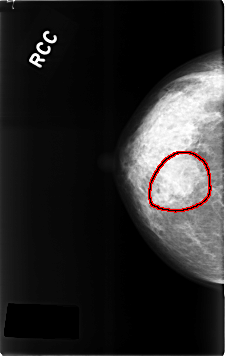

C_0314_1.RIGHT_CC

RIGHT_CC LINES 4616 PIXELS_PER_LINE 2928 BITS_PER_PIXEL 12 RESOLUTION 50 OVERLAY

FILE: C_0314_1.RIGHT_CC.OVERLAY

TOTAL_ABNORMALITIES 1

ABNORMALITY 1

LESION_TYPE MASS SHAPE LOBULATED MARGINS OBSCURED

ASSESSMENT 3

SUBTLETY 4

PATHOLOGY BENIGN

TOTAL_OUTLINES 1

BOUNDARY